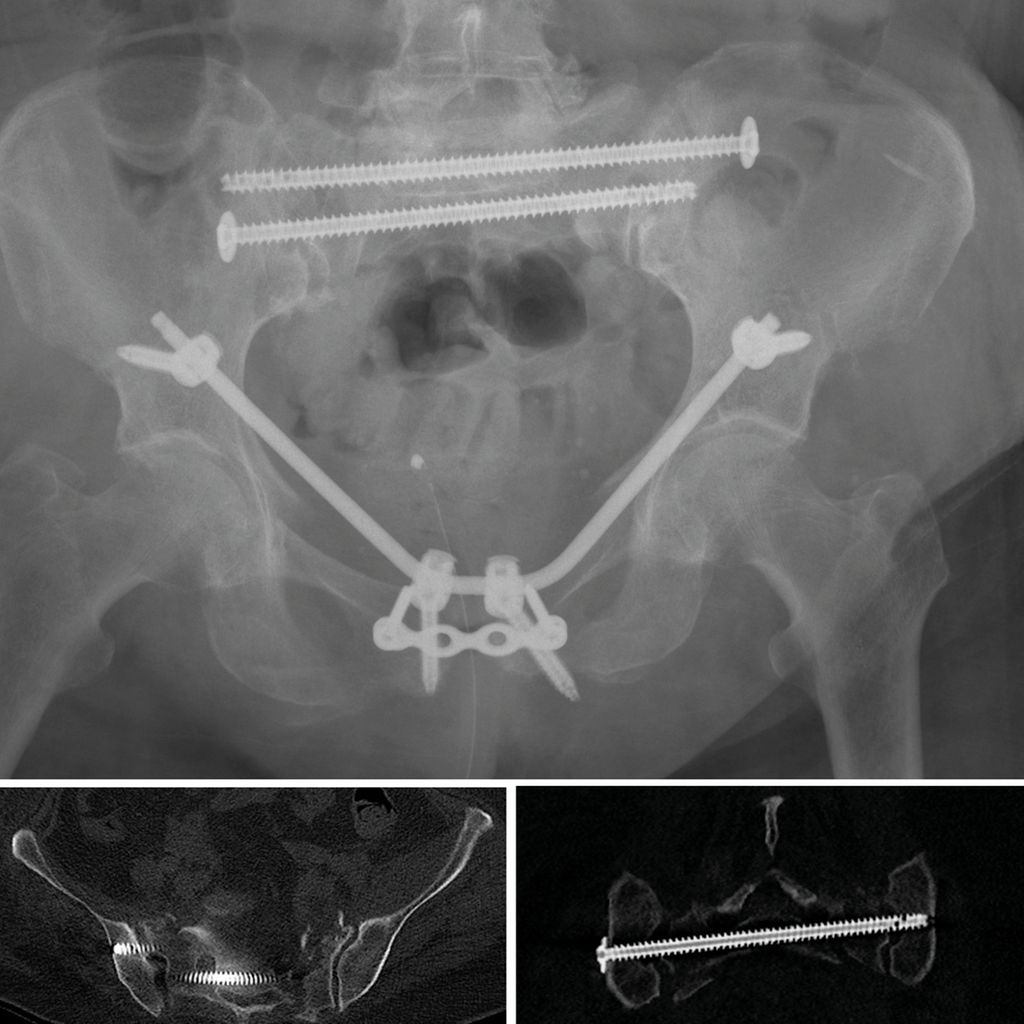

From www.universimed.com

Die Navigation in der Beckenchirurgie mittels LOOPX Orthopädie Loop X Karlsruhe 2021 | 08:00 uhr 3 minuten 18. mit loop x nutzt das städtisches klinikum als erste klinik deutschlands einen mobilen roboter, der das operationsverfahren. soll das operieren revolutionieren: „loopx“ heißt das gerät, mit dem der leitende neurochirurg am städtischen klinikum, uwe spetzger, zum ersten mal operieren konnte. Somit kann der eingriff präziser vonstattengehen. Loop X Karlsruhe.